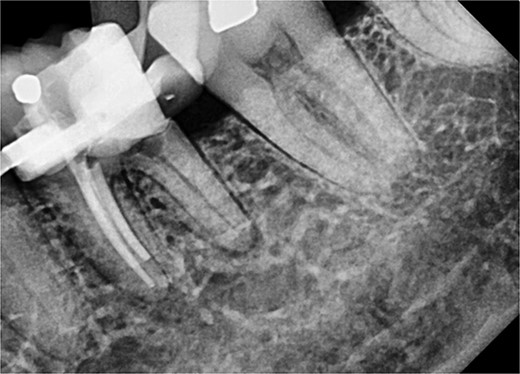

Non-surgical root canal treatment was initiated under local anesthesia and rubber dam isolation. Pulp extirpation was performed on all canals (mesio-buccal (MB), mesio-lingual (ML), and distal (D)). The MB and ML canals were instrumented using ProTaper Gold files and obturated with a bioceramic sealer (iRoot SP). The orifices were sealed with glass ionomer cement (Fuji IX) (Fig. 3).

Periapical radiograph of tooth 36 with obturation on MB and ML canals.